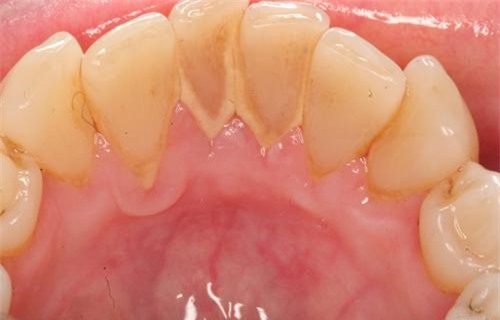

Cao răng (hay vôi răng) là mảng bám đã được vôi hóa bởi hợp chất muối calcium phosphate trong nước bọt. Thông thường mảng bám cần tồn tại trong miệng khoảng 1 tuần để biến thành cao răng. Vì vậy, nếu chúng ta làm vệ sinh răng miệng kĩ và thường xuyên thì cao răng sẽ không còn cơ hội hình thành. Cao răng thường tập trung ở cổ răng, có màu trắng đục, ở những người hút thuốc lá thì cao răng nhuộm màu vàng nâu, gây mất thẩm mỹ.

Cao răng có 2 loại là cao răng thường và cao răng huyết thanh. Cao răng thường như đã mô tả ở trên, khi cao răng thường gây nên viêm lợi tại chỗ, lợi vùng viêm đó sẽ tiết dịch viêm và chảy máu, máu đó ngấm vào cao răng thường tạo nên màu nâu đỏ, lúc này mảng cao răng đó được gọi là cao răng huyết thanh.

Tốc độ tạo cao răng ở mỗi người một khác, sự hình thành của nó bị ảnh hưởng của những thành phần có trong nước bọt, thói quen ăn uống, thói quen vệ sinh răng miệng. Sau khi đánh răng sạch khoảng 48 giờ là thời gian hình thành cao răng nhanh nhất, cao răng có màu nâu hoặc đen.